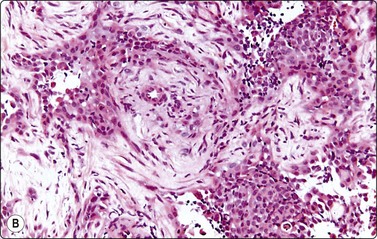

Wilms’ tumor (Figs 12.27 and 12.28)103-105

image

Fig. 12.27 Wilms’ tumor

Biphasic tumor; cohesive tubular structure and undifferentiated mesenchymal cells (MGG, HP).

Fig. 12.28 Wilms’ tumor

Small round cell tumor pattern of undifferentiated blastema (A, MGG; B, Pap, HP).

Criteria for diagnosis

Numerous undifferentiated small cells, single and in tight clusters (blastema),

Small, round or ovoid, hyperchromatic nuclei; multiple small nucleoli,

Scanty cytoplasm,

Epithelial differentiation: rosettes, tubular structures or cords (commonly present),

Mesenchymal differentiation: spindle cells (sometimes present).

Wilms’ tumor (nephroblastoma) is predominantly a tumor of childhood and is dealt with in more detail in Chapter 17. However, it can also occur in adults. Smears are usually dominated by small, undifferentiated malignant cells representing blastema. A specific diagnosis requires in addition evidence of epithelial and mesenchymal differentiation, but this may only be obvious in the better-differentiated tumors. Individual cells generally appear undifferentiated. Epithelial differentiation is suggested by microarchitectural patterns such as rosettes, tubules or cords (Fig. 12.27), which are not always present in smears. Correlation with clinical and radiological findings is important. The diagnosis may be supported by ancillary studies. The results of immunostaining are variable, depending on differentiation. Useful markers are vimentin, LMWCK, EMA and WT1. Heterogeneous cytogenetic abnormalities can be demonstrated in a proportion of tumors.